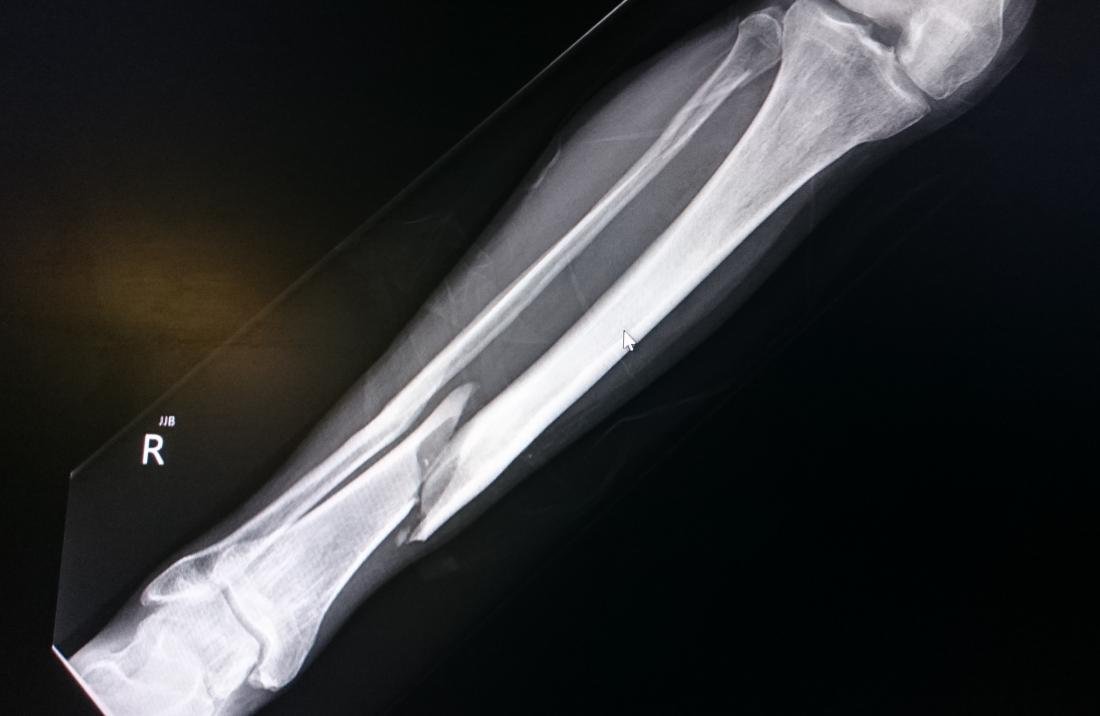

3. Fractures: Fractures account for 50% of compartment syndromes.

- Tibial fractures are the most common fracture causing the syndrome, but any extremity fracture can lead to increased compartment pressure.

- Open fractures do not preclude the development of compartment syndrome. Compartment syndrome can occur in the absence of fracture with soft-tissue injury, ischemia and reperfusion, prolonged compression (i.e., patients with altered level of consciousness), burns, and operative osteotomies.